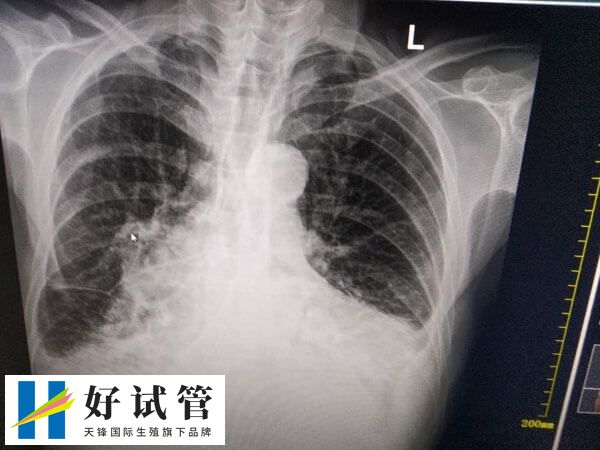

若疼痛持续不缓解或伴有发热、呼吸困难等异常,需警惕其他疾病(如胸膜炎、肋间神经痛等),建议及时就医排查。